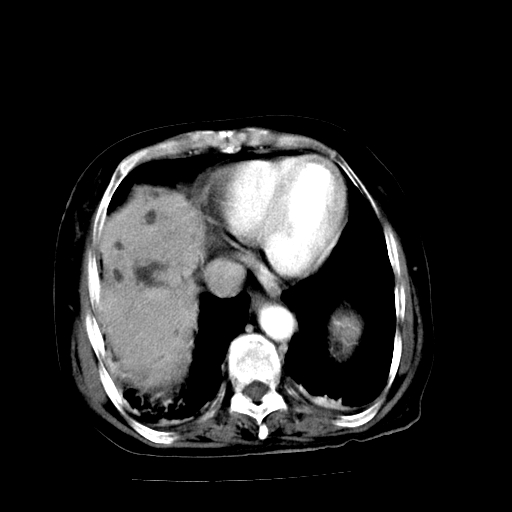

以下是引用随光逐影在2009-4-7 8:21:00的发言:[br]肝内外胆管多发性结石并肝内外胆管扩张;胆系感染。